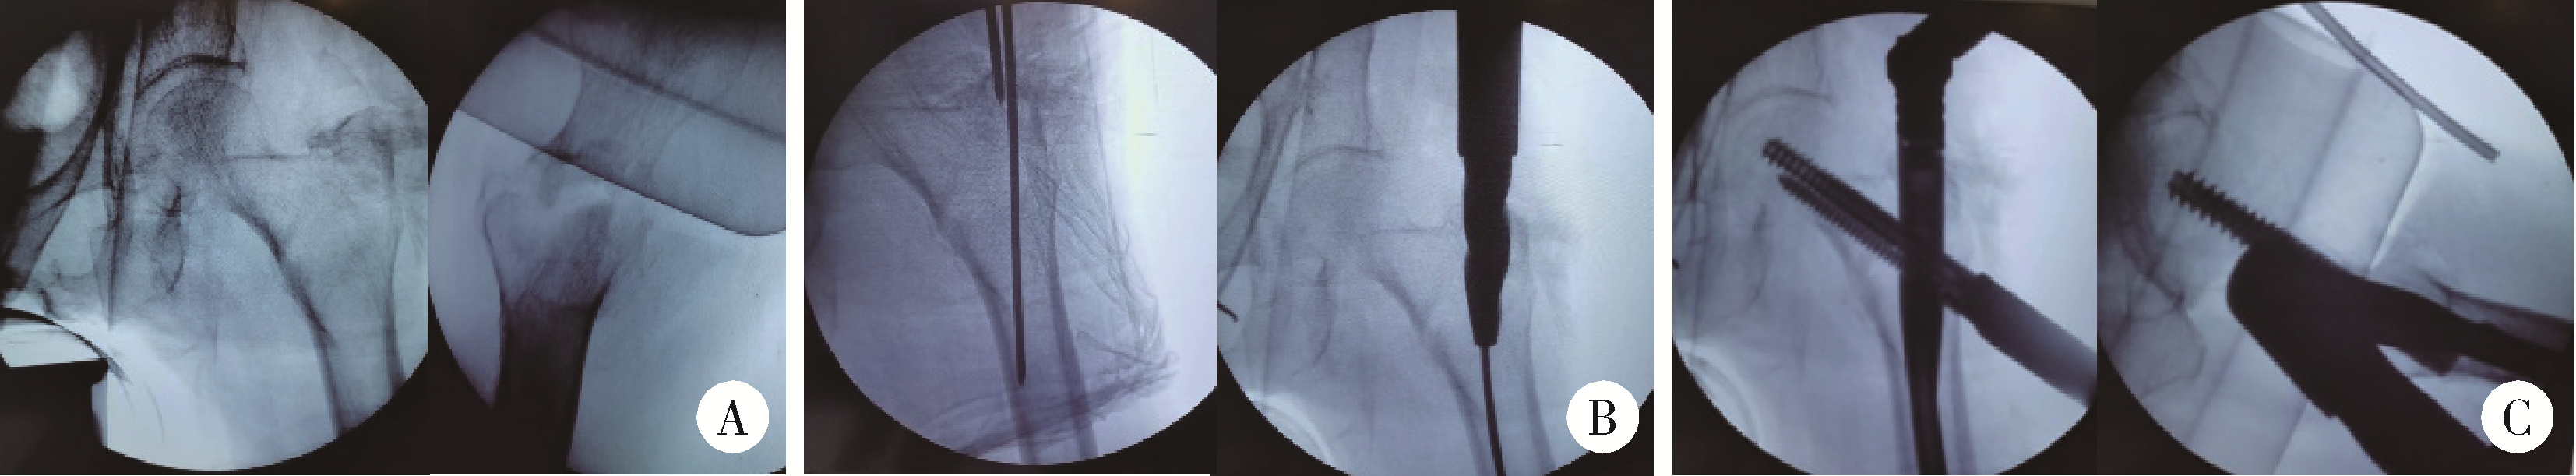

Figure 2

X-ray in closed reduction and internal fixation of femur intertrochanteric fracture of paitient A, following closed reduction, the X-ray of the left hip confirmed a well-reduced fracture; B, after inserting the guide pin into the femoral medullary cavity, reaming was performed; C, subsequently, the proximal femoral intramedullary nail and lag screw were inserted, and an X-ray of the femur was taken."